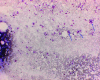

Unexpected finding on staging bone marrow aspirate for Hodgkin's lymphoma